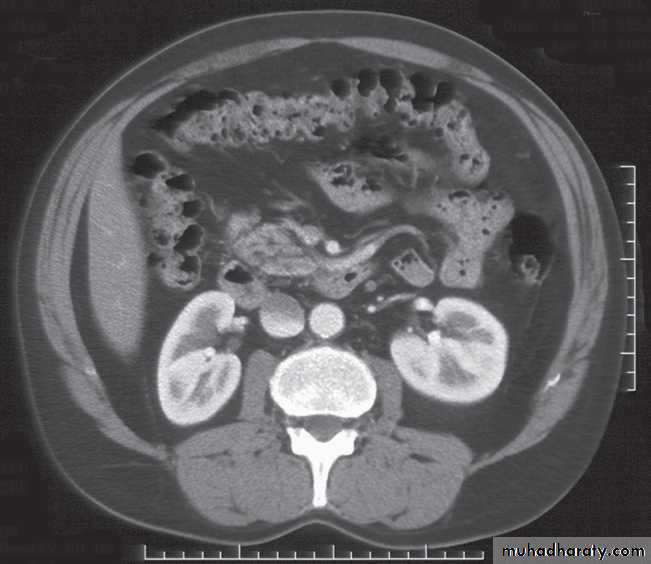

Computed tomography urography

CT is initially performed without intravnous contrast medium (non-contrast CT or ‘CT KUB’) to identify calcification .indication and include:

(i) The early renal cortical enhancement phase.(ii) The homogeneous nephrogramphase; and

(iii)The delayed urographic phase, obtained

several minutes later to demonstrate

contrast within the collecting systems.